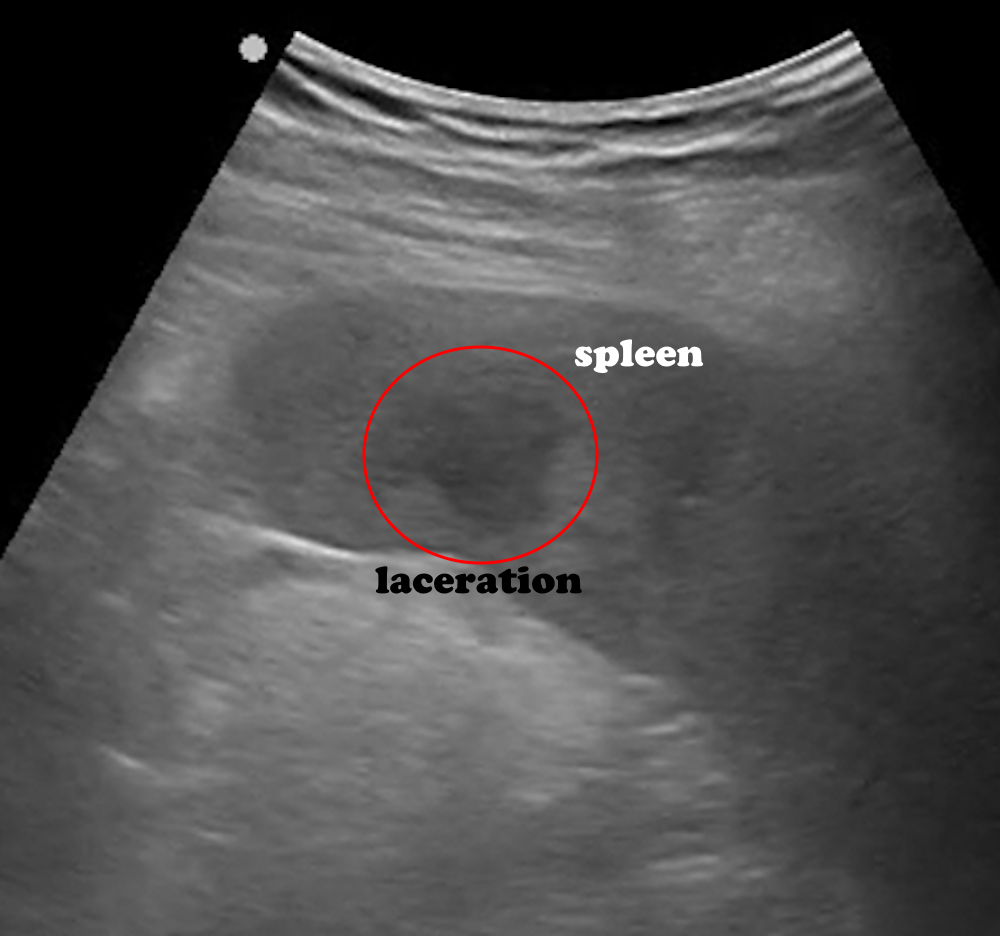

The spleen is located in the left upper abdominal quadrant, just beneath the diaphragm. Its anatomical relations are as follows: superiorly the diaphragm, anteriorly the fundus of the stomach, posteriorly the left kidney, and medially the tail of the pancreas (Figure 13). Compared to the liver, the spleen appears more hyperechoic and homogeneous. Its average dimensions are 10 cm in length, 7–8 cm in width, and 4.5 cm in thickness. For imaging, the patient lies in a supine position, and the probe is placed along the posterior axillary line through the left lower intercostal spaces. Disruption of the homogeneous echotexture is significant for identifying lacerations due to trauma (Figure 14), infarction, or the presence of perisplenic fluid.